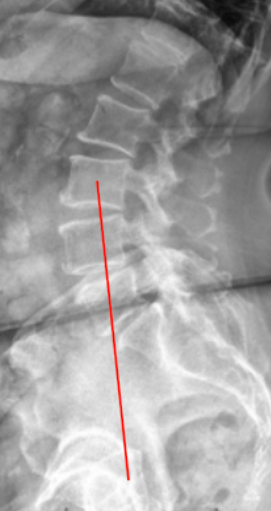

Ferguson’s Line, also known as the Weight-bearing Line of the Lumbar Spine, is a radiographic alignment reference used to evaluate sagittal load distribution through the lumbar spine and pelvis during standing posture.

When drawn correctly, Ferguson’s Line passes vertically from the center of the L3 vertebral body down through the sacrum. Its relative position on the sacral base indicates whether spinal loading is balanced (normal) or shifted (pathologic).

• From this midpoint, draw a vertical line perpendicular to the horizontal reference (ground level).

• This represents Ferguson’s Line or the weight-bearing line.

• Extend the line downward to intersect the sacrum and pelvis.

• Observe and record where the line passes through the sacral base:

• Normal: near the anterior third of the sacral base.

• Pathologic: anterior or posterior deviation relative to this zone.

• Normal alignment: line passes through anterior third of sacral base; balanced sagittal load distribution

• Posterior imbalance: line passes through posterior to the anterior third (toward mid-sacrum); load shift posteriorly, may indicate flat-back posture or compensatory pelvic retroversion

• Anterior imbalance: line passes anterior to sacral base; excessive anterior load, associated with hyperlordosis or spondylolisthesis

• Marked posterior imbalance: line passes posterior to sacrum entirely; global sagittal malalignment, often symptomatic

In a physiologic posture, the vertical load from L3 should fall through the anterior third of the sacral base to maintain efficient energy transfer and lumbosacral stability.